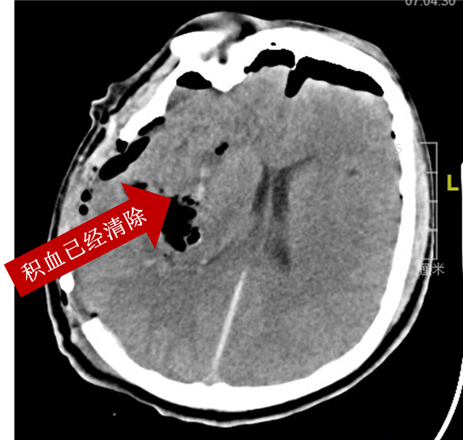

在神经内镜辅助下清除脑内血肿,手术进行3个小时,术后患者散大的瞳孔恢复正常。复查脑CT显示脑出血已完全清除。

王先生在术后第一天意识障碍减轻对疼痛有准确反应,愿王先生早日康复!